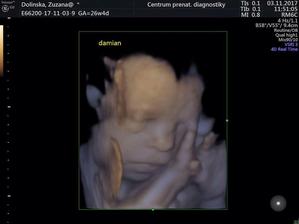

Nase dvojicky